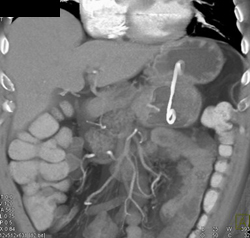

GIST Tumor